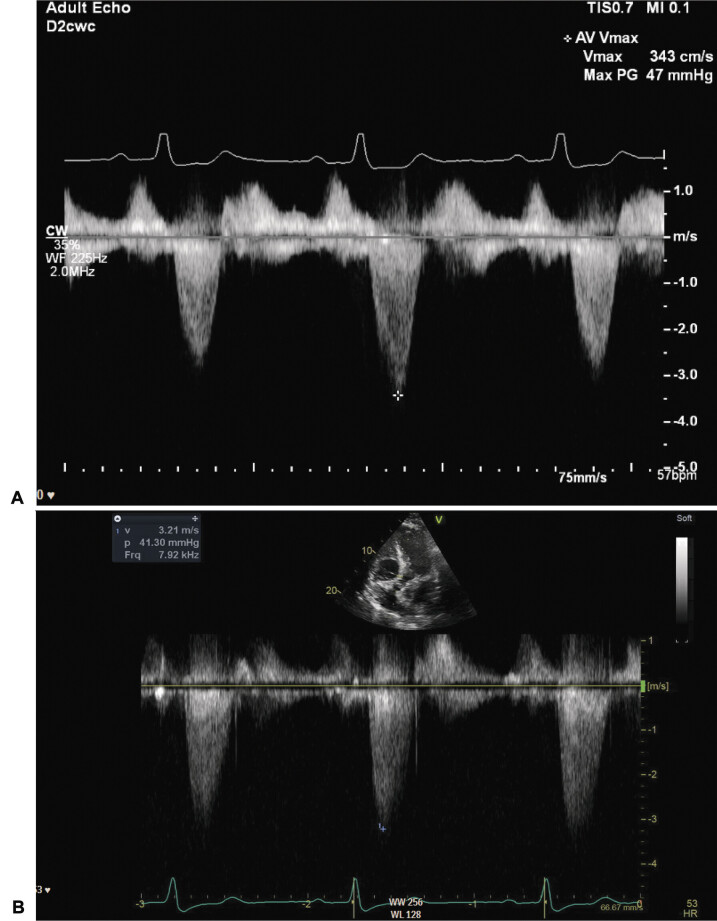

一位70岁的男性,由于左颈内动脉(ICA)闭塞而发生短暂性脑缺血发作(tia),他接受了颈外动脉到ICA的搭桥手术,该搭桥术后闭塞。在左心室流出道梗阻的情况下,经胸连续超声心动图优化后,患者出现失语,并以诱发高血压解决。

A 70-year-old man with transient ischemic attacks (TIAs) due to left internal carotid artery (ICA) occlusion underwent external carotid to ICA bypass which occluded postoperatively. He developed aphasia which resolved with induced hypertension optimized by using serial transthoracic echocardiography in the setting of left ventricle outflow tract obstruction.